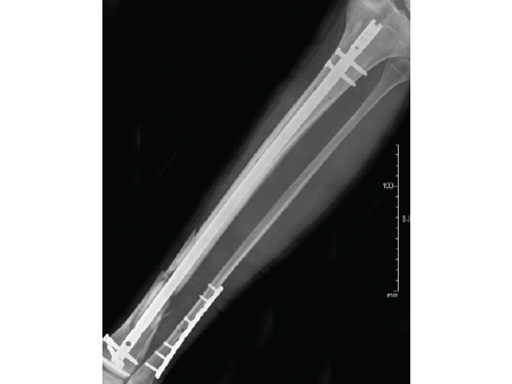

Clinical example of the first patient treated with the new ETN PROtect.

Case 1: A 33-year-old man with a third degree open fracture of his left tibia was initially treated with an external fixator and unilateral compartment release. He had undergone ACL reconstruction in the past.